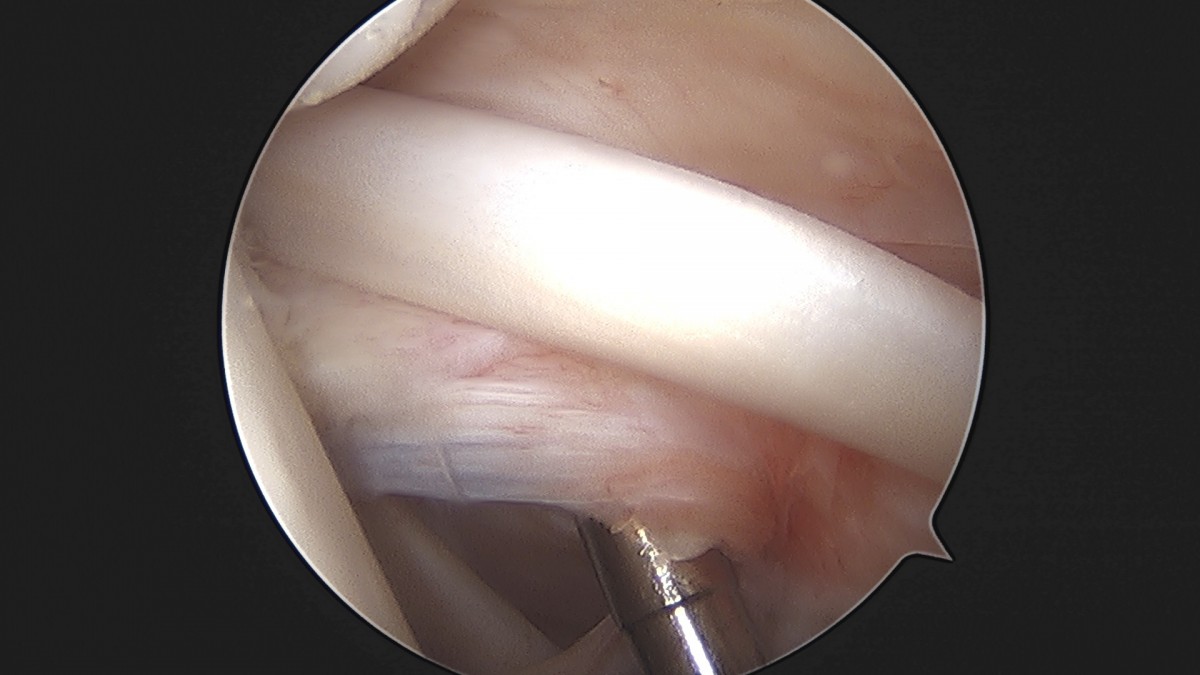

정지영원장님 어깨 관절낭 이완술 이상O 환자

dae765e4d9ac96aee867c9d6292d8784_1758009479_911.jpg